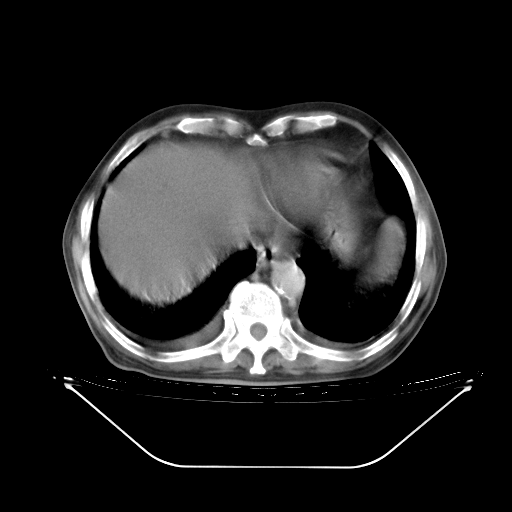

胸腹部CT,诊断意见:左上肺叶钙化灶、左侧胸膜局限性增厚并钙化、胆囊炎。描述部分肺组织呈磨玻璃样改变。